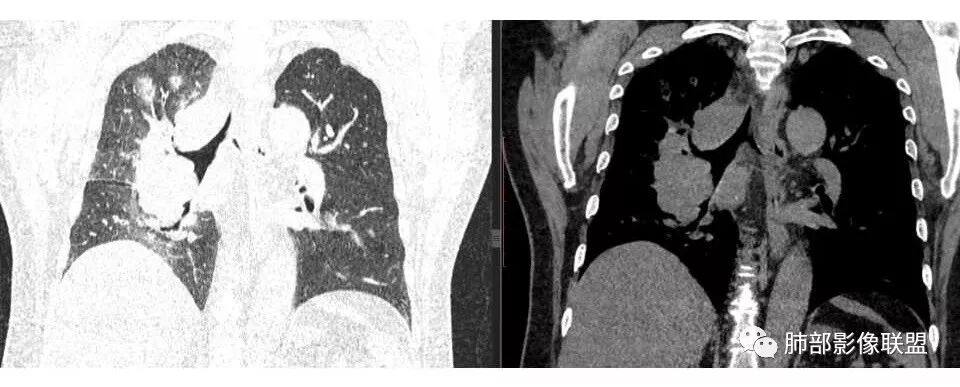

肺门及纵隔多发淋巴结。2L,4R,3区都有肿大淋巴结。

南边:有老师认为,血管前的这个应该是一个胸腺来源的。我觉得不是,为什么不符合胸腺来源呢,就看那个内乳动脉

双侧对比:右侧增粗,提示供血

但在内侧,不是外移

所以我倾向于淋巴结可能

胸腺瘤按理推压外移的多

而且胸腺癌转移不以淋巴结为主,如果淋巴结显著,按理周围侵袭性比较强,淋巴结也应该以附近为主,不应该以肺门为主,不符合引流规律。

局限性中央间质增厚,考虑癌性淋巴管炎

部分区域有结节感

右侧胸膜增厚

南边: 而且肺癌,一定受叶段的局限,这一例跨越右肺门,提示多个淋巴结融合

1.右肺上叶不规则结节影,右肺门及纵隔多结节并形成巨大块影,密度均匀,沿途支气管明显狭窄。

原发灶小或隐匿,肺门纵隔淋巴结异常增大,所谓“娘小崽大”常见于肺小细胞癌!

2.右肺小叶间隔增厚伴微小结节,提示癌性淋巴管炎。